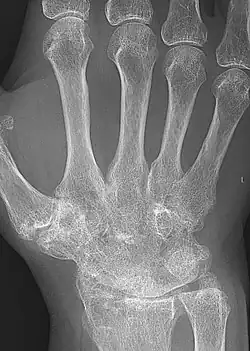

Ankylosis (from Greek ἀγκύλος (ankulos) 'bent, crooked') is a stiffness of a joint due to abnormal adhesion and rigidity of the bones of the joint, which may be the result of injury or disease. The rigidity may be complete or partial and may be due to inflammation of the tendinous or muscular structures outside the joint or of the tissues of the joint itself.[1]

When the structures outside the joint are affected, the term "false ankylosis" has been used in contradistinction to "true ankylosis", in which the disease is within the joint. When inflammation has caused the joint-ends of the bones to be fused together, the ankylosis is termed osseous or complete and is an instance of synostosis. Excision of a completely ankylotic shoulder or elbow may restore free mobility and usefulness to the limb. "Ankylosis" is also used as an anatomical term, bones being said to ankylose (or anchylose) when, from being originally distinct, they coalesce, or become so joined that no motion can take place between them.[1]

- Other forms of arthritis may sometimes also lead to ankylosis, including rheumatoid arthritis and reactive arthritis

- Osteoarthritis usually confers osteophyte formation, which may eventually fuse across joints. Osteoarthritis is believed to be caused by mechanical stress on the joint and low-grade inflammatory processes.[3]